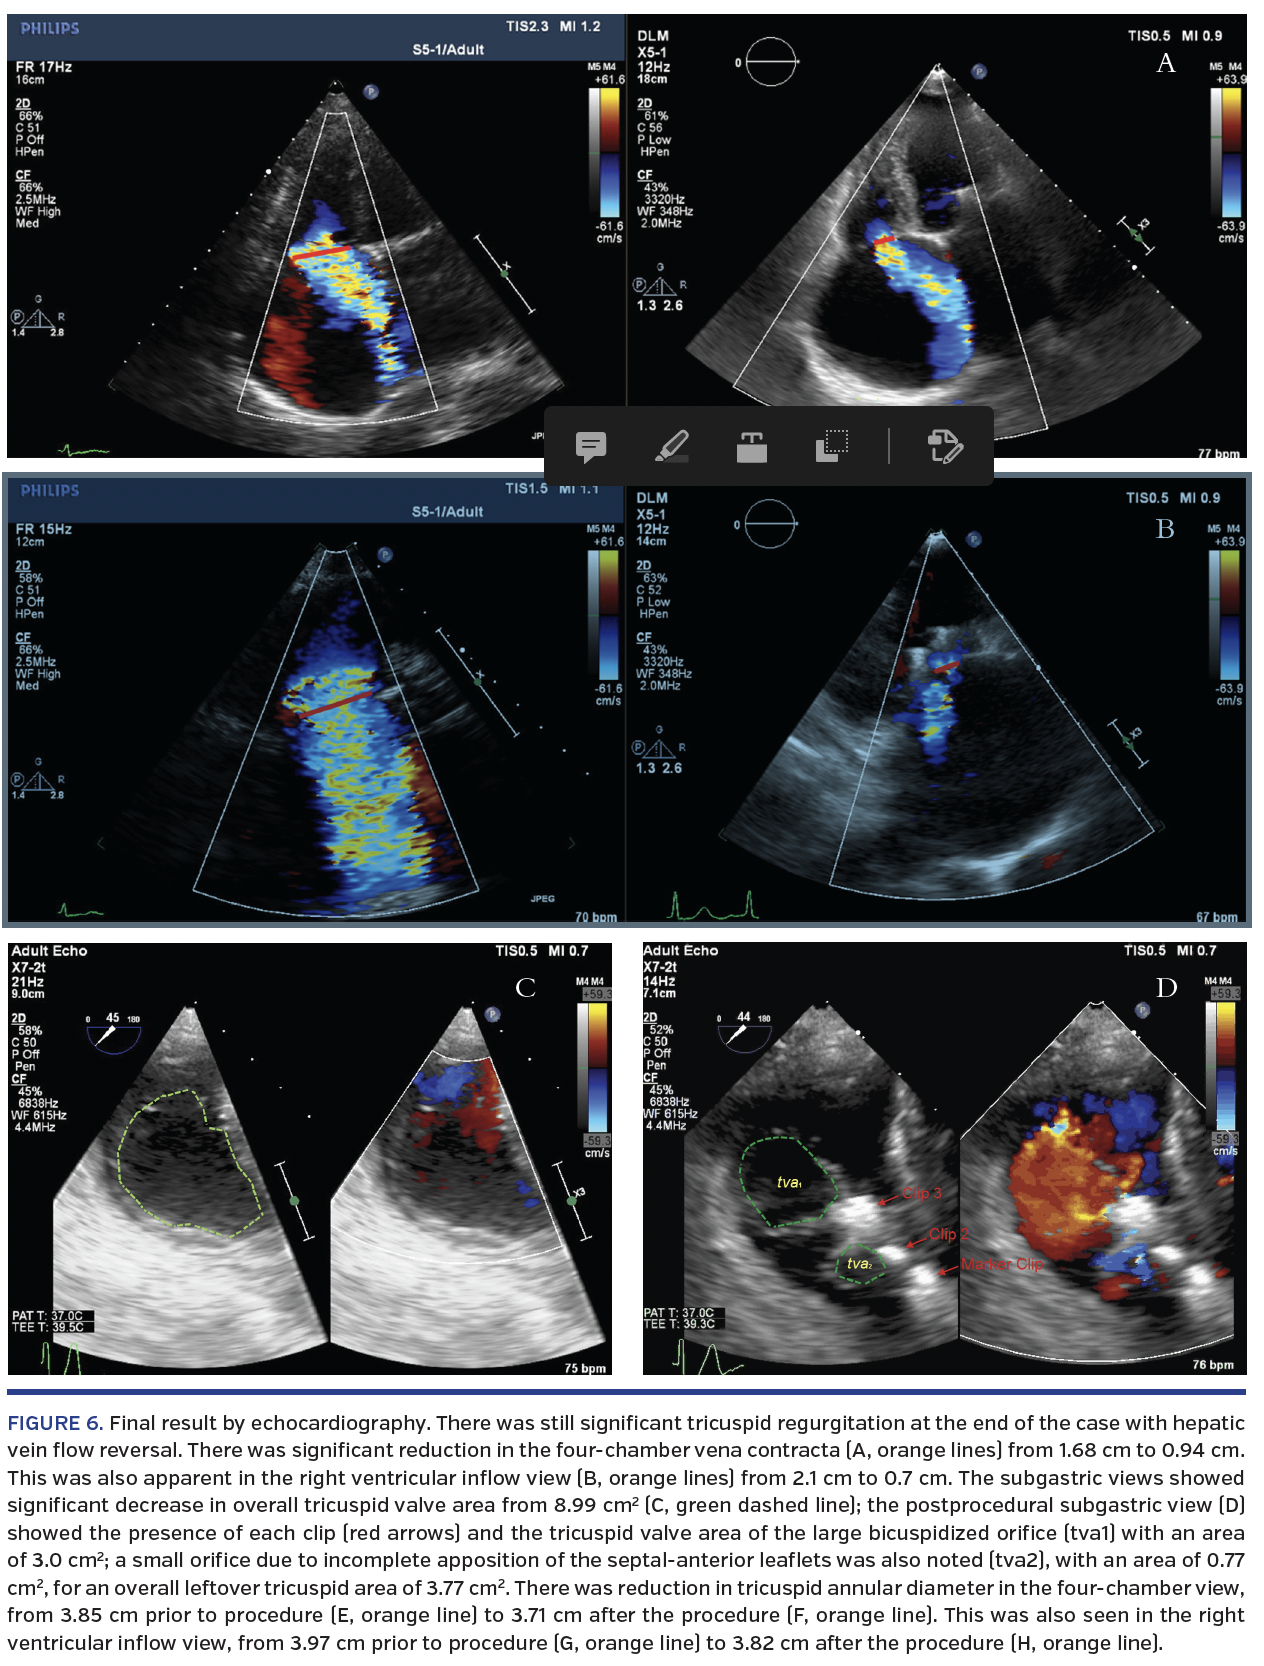

At the end of the procedure, there was almost full closure of the anterior-septal commissure; thus, bicuspidization of the tricuspid valve was achieved (Figure 6). There was still significant severe tricuspid regurgitation with systolic flow reversal in the hepatic veins. However, there was a reduction in the vena contracta from 1.68 cm to 0.94 cm in the four-chamber TEE view and from 2.1 cm to 0.7 cm in the right ventricular inflow TEE view. There was also a decrease in tricuspid valve area from 8.9 cm2 to 3.77 cm2. In addition, a reduction in tricuspid valve dimensions was seen.

In this paper, we describe a periprocedural imaging algorithm to facilitate grasping the leaflets of the tricuspid valve using a MitraClip device (Table 1). From an echocardiographic standpoint, the evaluation begins with three-dimensional TEE imaging to understand initial maneuvering to the correct leaflet pair and gross rotation for perpendicularity. The TEE transgastric view is then obtained to evaluate clip position along the commissural-central axis, with use of the “x-plane” to add to the ability to understand perpendicularity. After this, an appropriate two-dimensional view allows fine-tuning of rotation, including correction of a septal hugger guide catheter, as described above in Figure 4. Adjunctive fluoroscopic imaging can be used to show how subsequent clips can relate to the first marker clip location and position. The LAO and AP-RAO views show the clips in two different directions, which can facilitate guide positioning before clip advancement and provide assistance when TEE image acquisition is challenging.